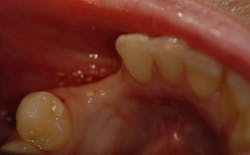

A CBCT scan was taken and imported into the implant planning software. A digital diagnostic wax-up was done by inserting teeth Nos. 26 and 27 into ideal position. With an extremely thin ridge and lack of crestal height, it was determined that space was available for a single implant. Placement was planned for a screw-retained prosthesis with an anterior cantilever (figures 3 and 4).